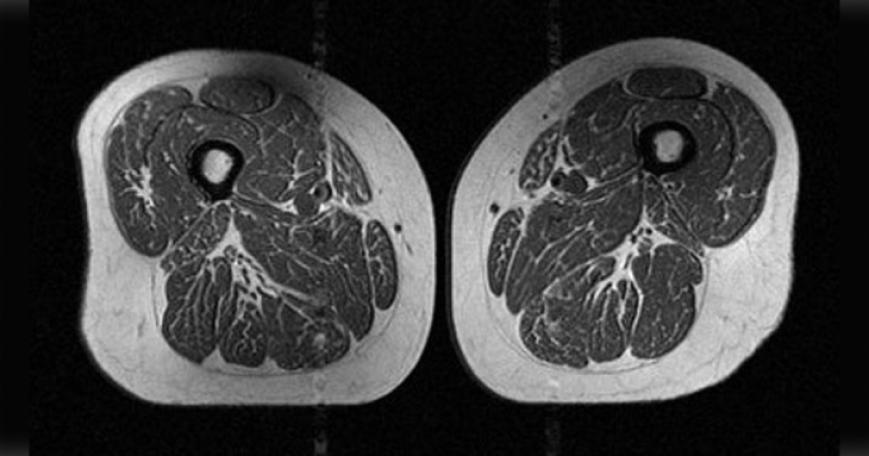

|生活近期一項研究指出,人類飲食若攝取即食穀片、糖果、含糖飲料等超加工食品的比例過高,會導致脂肪滲透進肌肉纖維,形成類似「雪花牛排」的「脂肪浸潤」。這種脂肪細胞會阻礙肌肉生長,而肌肉無力正是罹患退化性膝關節炎的主因。

近期一項研究指出,人類飲食若攝取即食穀片、糖果、含糖飲料等超加工食品的比例過高,會導致脂肪滲透進肌肉纖維,形成類似「雪花牛排」的「脂肪浸潤」。這種脂肪細胞會阻礙肌肉生長,而肌肉無力正是罹患退化性膝關節炎的主因。